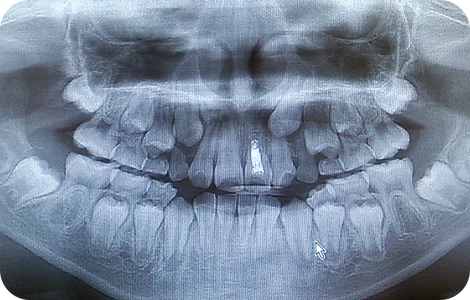

通常は、発育空隙と言って、写真のようなスペースがあるのが正常です。

なぜなら、永久歯の方が乳歯よりも大きいので、スペースの無い奇麗な歯並びですと、将来、叢生(乱杭歯=デコボコのはならび)になる可能性が高いからです。